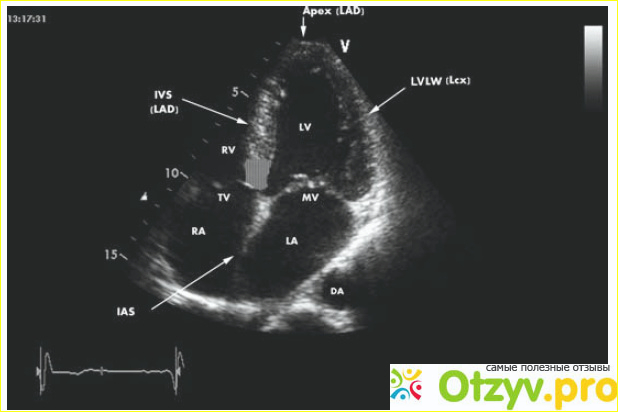

Ультразвуковое исследование сердца

Ультразвуковое исследование сердца или эхокардиограмма является эффективным и достаточно безопасным методом, у которого отсутствуют какие-либо противопоказания. Это обследование проводят всегда профессиональным спортсменом, а также тем людям, которые находятся в условиях постоянных увеличенных физических нагрузок. Преимущество этого метода в том, что у него очень высокая информативность, и можно сказать что это важнейший метод диагностирования заболеваний сердечно-сосудистой системы.